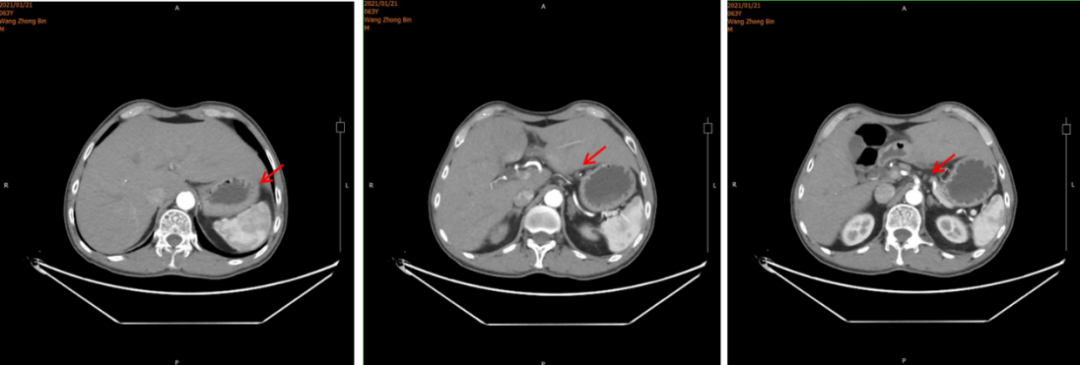

2021年1月21日腹部CT:胃窦癌征象,伴胃周、腹膜后增大淋巴结,请结合临床;肝右叶肝内胆管结石或钙化灶;左侧肾上腺强化不均。

图1.腹部CT

2021年3月5日术后化疗时上腹部增强MRI发现疾病进展,出现新发肝转移癌。MRI示:胃体积减小,肝脏局部体积减小,肝左叶见一类圆形轻度环形强化影,平扫显示不清,最大径约16.6mm。诊断建议:肝、胃术后改变,肝左叶环形强化影,新发肝转移。(图4)

图4. 上腹部增强MRI